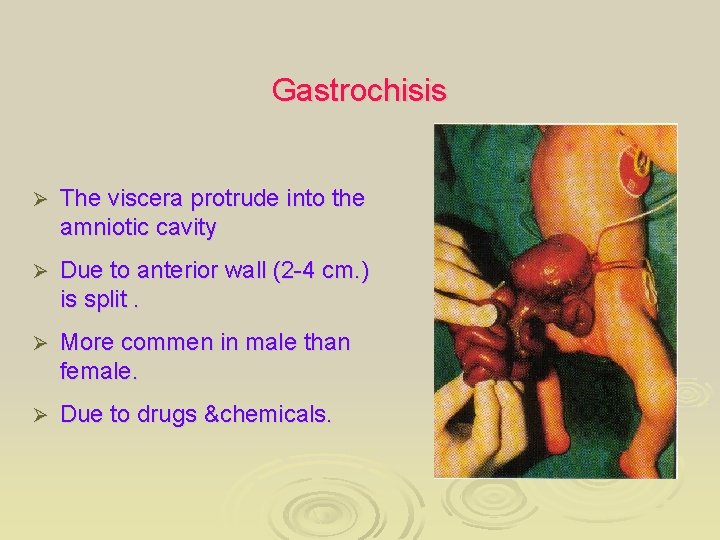

Gastrochisis Ø The viscera protrude into the amniotic cavity Ø Due to anterior wall (2 -4 cm. ) is split. Ø More commen in male than female. Ø Due to drugs &chemicals.